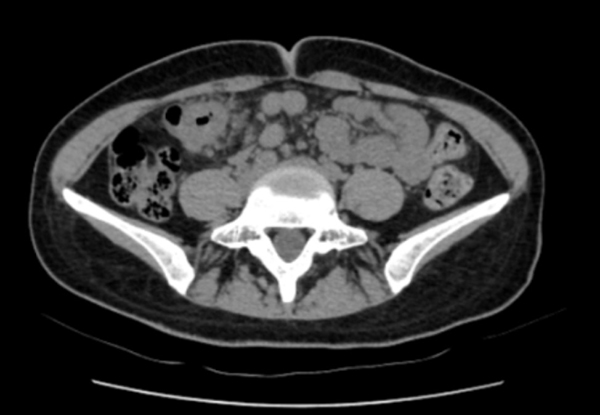

“脐周疼痛对应的多是小肠问题,右上腹的包块却指向肝胆、结肠等器官,这两者对不上。”医生立刻警觉起来,当即安排王女士做腹部CT检查。影像结果很快出来:结肠近肝曲处肠壁可疑增厚,肠腔狭窄——这个信号让诊疗团队的神经瞬间紧绷。